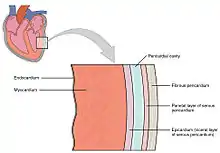

The heart wall is made up of three layers: the inner endocardium, middle myocardium and outer epicardium. These are surrounded by a double-membraned sac called the pericardium.

The innermost layer of the heart is called the endocardium. It is made up of a lining of simple squamous epithelium and covers heart chambers and valves. It is continuous with the endothelium of the veins and arteries of the heart, and is joined to the myocardium with a thin layer of connective tissue.[7] The endocardium, by secreting endothelins, may also play a role in regulating the contraction of the myocardium.[7]

The middle layer of the heart wall is the myocardium, which is the cardiac muscle—a layer of involuntary striated muscle tissue surrounded by a framework of collagen. The cardiac muscle pattern is elegant and complex, as the muscle cells swirl and spiral around the chambers of the heart, with the outer muscles forming a figure 8 pattern around the atria and around the bases of the great vessels and the inner muscles, forming a figure 8 around the two ventricles and proceeding toward the apex. This complex swirling pattern allows the heart to pump blood more effectively.[7]

Pericardium

The pericardium is the sac that surrounds the heart. The tough outer surface of the pericardium is called the fibrous membrane. This is lined by a double inner membrane called the serous membrane that produces pericardial fluid to lubricate the surface of the heart.[30] The part of the serous membrane attached to the fibrous membrane is called the parietal pericardium, while the part of the serous membrane attached to the heart is known as the visceral pericardium. The pericardium is present in order to lubricate its movement against other structures within the chest, to keep the heart's position stabilised within the chest, and to protect the heart from infection.[31]